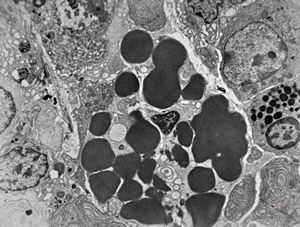

M,35y. | duodenum … lipid malabsorption - susp. hypo-beta-lipoproteinemia

jejunum … lipid malabsorption

duodenum … lipid malabsorption

F,8m. | lipid malabsorption - large lipid droplets in enterocytes … semithin section

lipid malabsorption - large lipid droplets in enterocytes … semithin section

lipid malabsorption - large lipid droplets in enterocytes and propria … HE